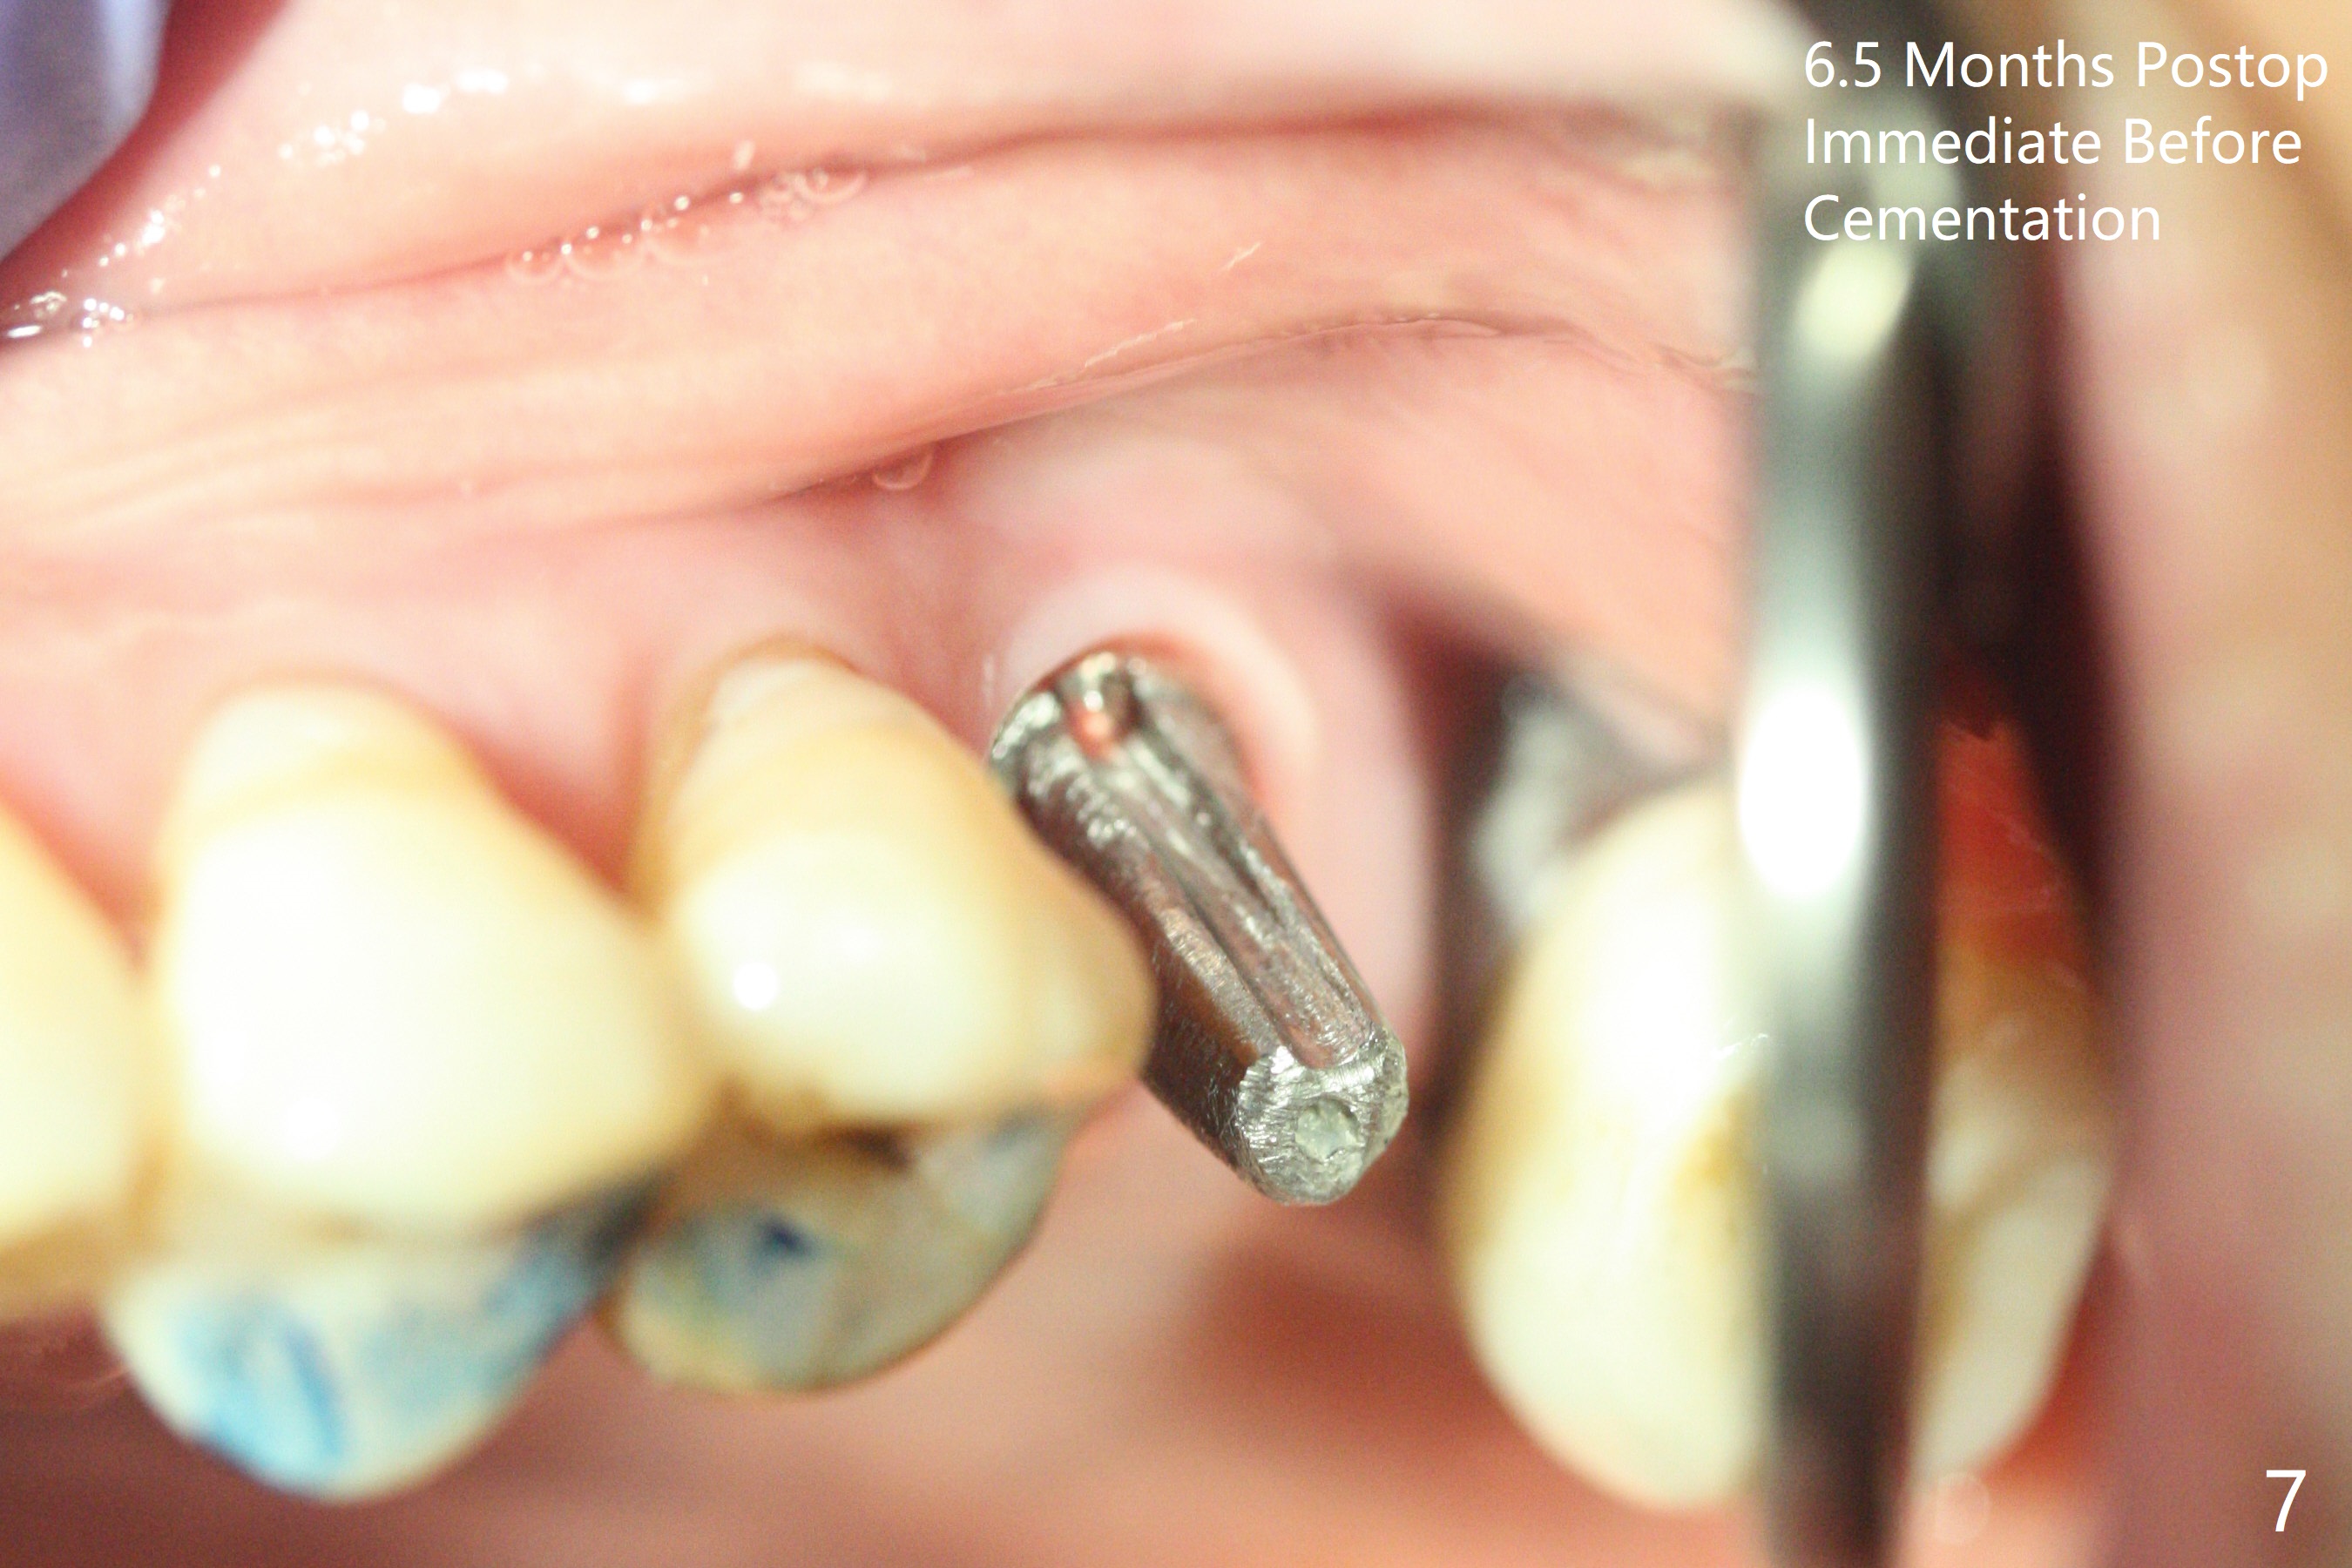

After osteotomy with guide at #14 (4.5x7.3 mm last drill with 1 O-ring/10.5 mm offset for bone-level implant), a 5x11 mm tissue-level tap is used with allograft for sinus lift (Fig.1). With one more round of allograft for sinus lift, a 5x11 mm tissue-level implant is placed with ~ 50 Ncm (Fig.2). CBCT 3-D images (Fig.3 (palatal view), 4 (distal view) (D: distal)) and coronal section (Fig.5 (P: palatal)) show the bone graft in the sinus (*). The patient returns for restoration 5 months postop in spite of running out insurance benefits because of discomfort with the immediate provisional. When the latter is removed (Fig.6), the gingiva is erythematous. It appears that the implant was placed deep. The abutment is removed for easy local oral hygiene. A healing cuff will be used or the implant will be reversely torqued. If the former is placed, a 4 mm longer abutment (4.5x9 mm) should be used to increase crown retention using temp bond . In fact the provisional forms a nice gingival cuff before cementation (Fig.7,8). Return to Upper Molar Immediate Implant, Prevent Molar Periimplantitis (Protocols, Table), Trajectory 18 Xin Wei, DDS, PhD, MS 1st edition 04/22/2019, last revision 02/28/2020